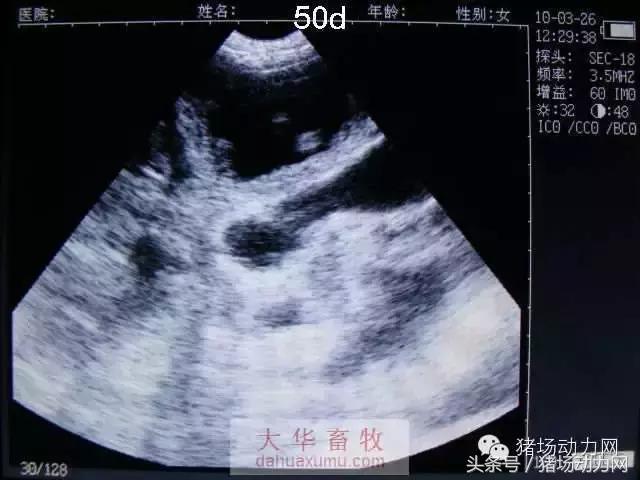

怀孕中期:41天——80天

以下为怀孕母猪21天到90天之内的变化图:

50天